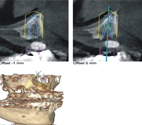

植牙重視的是人工牙根植進骨頭的位置,會擔心是否植入上顎竇造成後續可能有人工牙根不穩導致失敗、口鼻竇相通或是鼻竇炎感染的風險,也會擔心是否植入的位置離臨近的牙根太近,或是角度不對,這些可能影響未來假牙的美觀和吃東西時人工牙根受力的狀況導致使用時間縮短,這些擔憂在以往都需要藉由醫師的經驗和熟練度來克服,然而現在便能配合電腦輔助系統在手術前就暸解骨頭的厚度和高度(如:圖二),知道是否需要在植牙前補骨頭,也可以模擬植牙植入的位置並製作出導引板,有導引板就能依據導引板的指示去定位植牙的位置和角度,降低手術時的失誤率,大幅度的提升植牙的精準度。

圖二、電腦輔助模擬植牙手術定位